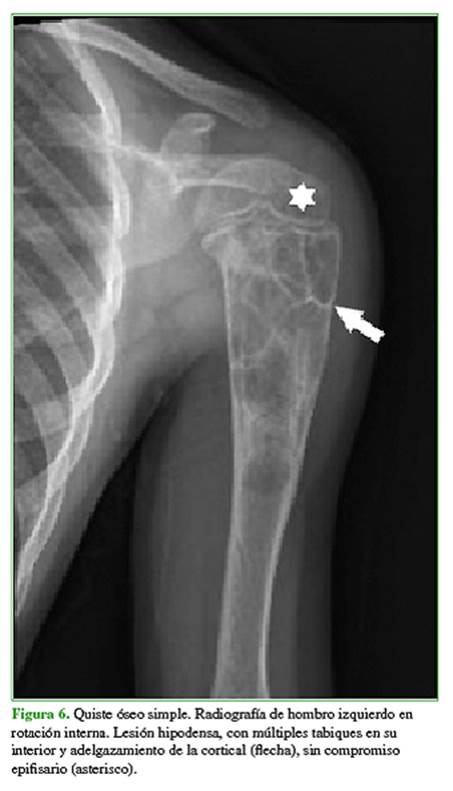

Los diagnósticos diferenciales más frecuentes son focos de hiperplasia de médula ósea grasa, displasia fibrosa (Figura 5), quiste óseo simple o aneurismático (Figura 6), lesiones condrales (encondroma, condrosarcoma) (Figura 7), infarto óseo antiguo, necrosis avascular (Figura 8) y fibroma condromixoide (Figura 9).